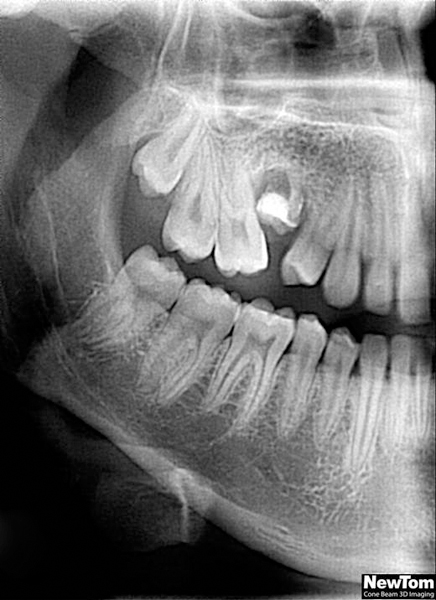

3D DVT - NewTom

Je speciální zubní digitální tříprostorový tomograf (3D), který umožňuje na základě jediného snímkování vytvořit všechny typy RTG zobrazení, které jsou pro lékaře potřebné. Díky používané technologii tzv. „kuželového paprsku“ a speciálním senzorům je výrazně zmenšená dávka záření - o více jak 80% proti klasickému CT vyšetření. To je významné zejména u dětí. Pomocí tohoto přístroje je možné zjisti skutečnou situaci v čelistních kostech pacienta tedy množství kosti - můžeme změřit skutečnou šířku i výšku kosti, i kvalitu kosti (hustotu) v místě uvažované implantace. 3D (tříprostorové) zobrazení umožňuje zvýšit prostorovou představu operatéra ještě před vlastní operací a zároveň pacientovi lépe objasnit a ukázat oblast plánovaného zavedení implantátu.

Pacient „neumí číst“ RTG snímky, ale díky 3D zobrazení vidí „svoji skutečnou čelist“ - např. jak je nízká či úzká, vidí průběh nervu nebo velikost čelistní dutiny, což mu umožní i pochopení nutnosti v některých případech provést pomocné zákroky ještě před vlastním zavedením implantátu (viz. kostní štěp, sinus lift, kostní granulát...).

Vyšetření pomocí tohoto přístroje používáme i ve stomatochirurgii (zlomeniny čelistí, zuby moudrosti, cysty, onemocnění čelistního kloubu), ortodoncii (retinované zuby, nadpočetné zuby), parodontologii atd.